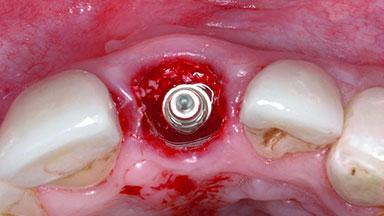

Replacement of a Failing Upper Left Central Incisor: Immediate Placement of an RC Bone Level Implant and Provisionalization

A healthy 23-year-old female patient was referred for a consultation on replacing tooth 21 with an implant-supported restoration. The patient had recently moved to the area and reported a history of endodontic and periodontal treatment for tooth 21. The tooth had been deemed non-restorable by her previous periodontist but since she was going to be moving, he recommended consulting to a dentist in her new city to continue her treatment. A review of her medical history yielded no significant findings and no known drug allergies. The analysis of her smile revealed a medium to high symmetrical smile line and a slightly discolored tooth 21.